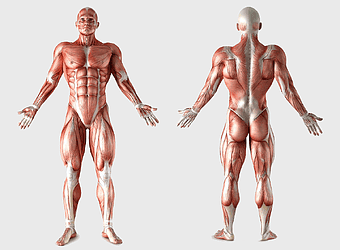

human anatomy diagram, muscular system illustration, human body muscles, fitness anatomy chart, skeletal muscle structure, human physiology study, muscle group analysis -

muscular system illustration, human anatomy diagram, fitness professional figure, skeletal muscle structure, muscular development, human body musculature, anatomical study -

human anatomy back muscles, male muscle structure, human anatomy illustration, man anatomy diagram, anatomical muscle chart, full-body muscle map, posterior muscle view -

human muscular system anatomy, fitness professional bodybuilder, human body organ systems, skeletal muscle tissue, full-body muscle diagram, anatomical muscle structure, human physiology illustration -

human muscular system illustration, muscle anatomy human body, fitness professional bodybuilder, human back and abdomen muscles, anatomical muscle structure, human skeletal muscle system, detailed human muscle chart -